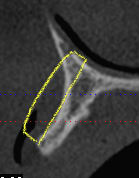

Comme le titre de ce sujet s'y prête bien et en attendant que le concept d'usinage des greffons allogéniques soit validé, je vous expose ma méthode pour adapter au mieux un greffon (allogénique ou autogène)

règles de base:

-on retouche prioritairement le greffon ailleurs que dans les zones où il doit redonner le maximum de volume

-il faut observer la forme du défaut osseux selon 3 axes: frontal, vertical et latéral et on adapte la forme du greffon pour chacune de ces vues

1°) frontalement: on regarde les berges mésiales et distales du défaut, elles peuvent être parallèles entre elles, convergentes ou divergentes, (voir vues ci-dessous)

et on taille les bords latéraux du greffon en fonction de ces berges.

2°) latéralement: il faut observer la forme générale de la concavité du défaut et on taille alors l'intrados du greffon pour épouser cette concavité générale et on prend garde de tailler le moins possible à l'endroit ou on a besoin de garder de l'épaisseur (généralement dans la partie coronaire du greffon)

3°) verticalement: on observe la forme générale de la concavité du défaut, cette concavité peut varier entre la partie coronaire du défaut et sa partie apicale. On reproduit la forme convexe correspondante à l'intrados du greffon

après ces 3 étapes le greffon est généralement déjà bien adapté.Il faut parfois cependant ajuster l'intrados dans les cas (nombreux) où il existe un gradiant de courbure des concavités de haut en bas et latéralement.

Pour des formes plus tarabiscotées, certains prennent l'empreinte de la forme du défaut avec de la cire à os pour mieux visualiser en positif les subtilitées géographiques du défaut.

Coupe xray transversale omynvk - Eugenol

Coupe xray transversale greffe m05aen - Eugenol

Coupe xray transversale greffe2 njaaal - Eugenol